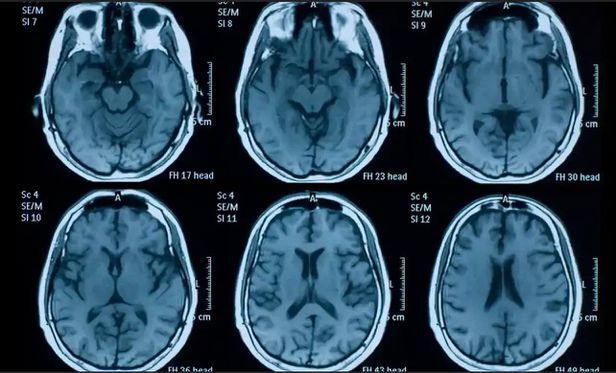

스터프에 따르면 연구팀은 영국의 유전자 정보 수집계획인 영국 바이오뱅크에 참여한 51~81세 785명의 뇌 변화를 조사했다. 이들 중 401명은 두 번의 뇌 영상 촬영 사이에 코로나19 양성 판정을 받았다.

코로나19에 감염된 후 이뤄진 뇌 영상 촬영의 경우 소요된 기간이 평균 141일로 연구팀은 이들을 통해 코로나19에 걸린 후 3개월 뒤에 뇌에 어떤 영향을 주는지를 살폈다. 그 결과 코로나19 환자는 뇌의 여러 부위에서 크기가 줄어드는 것으로 나타났다.

특히 안와전두피질과 해마곁이랑에서 회백질 두께가 감소했다. 감소 정도는 1.3~1.8% 정도였는데, 이는 정상적인 중년 성인의 연간 뇌용적 손실(0.2~0.3%) 정도와 비교된다는 설명이다.

안와전두피질은 인간 뇌의 4분의 1 이상을 차지하는 부위로 인지 정보와 감정 정보를 통합하는 역할을 한다. 대뇌 반구 아래에 있는 긴 이랑인 해마곁이랑은 후각, 사건 기억과 관련된 영역으로 알려져 있다.

나이가 많을수록 코로나19 감염으로 뇌 부위가 줄어드는 정도가 더 큰 것으로 나타났다. 연구진은 또 “후각 경로나 신경계 염증, 후각 상실로 감각 입력이 부족해지면서 퇴행성 질환이 나타날 수 있다”며 “코로나19에 영향을 받는 뇌 영역 중 어느 부위가 취약한지 추가 조사가 필요하다”고 말했다.